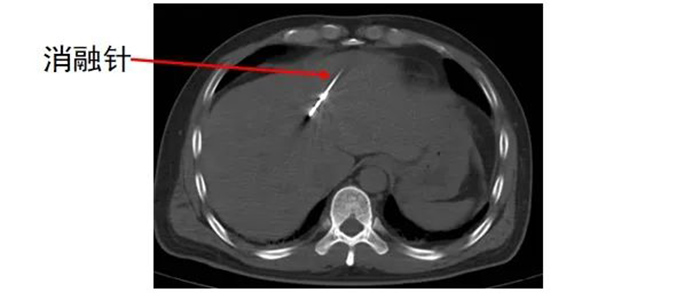

齐先生病灶临近大血管、重要脏器。厦门三院专家团队在CT引导下精准定位,经皮穿刺将微波消融针准确置入齐先生肝脏肿瘤部位,然后利用微波能量,使肿瘤组织内的水分子快速振动、摩擦产生热量,从而使局部温度迅速升高,让肿瘤细胞凝固性坏死。整个手术过程顺利,避免了严重并发症发生。

准确插入到病灶内,并避开了门静脉左支及分支,避免了出血并发症。